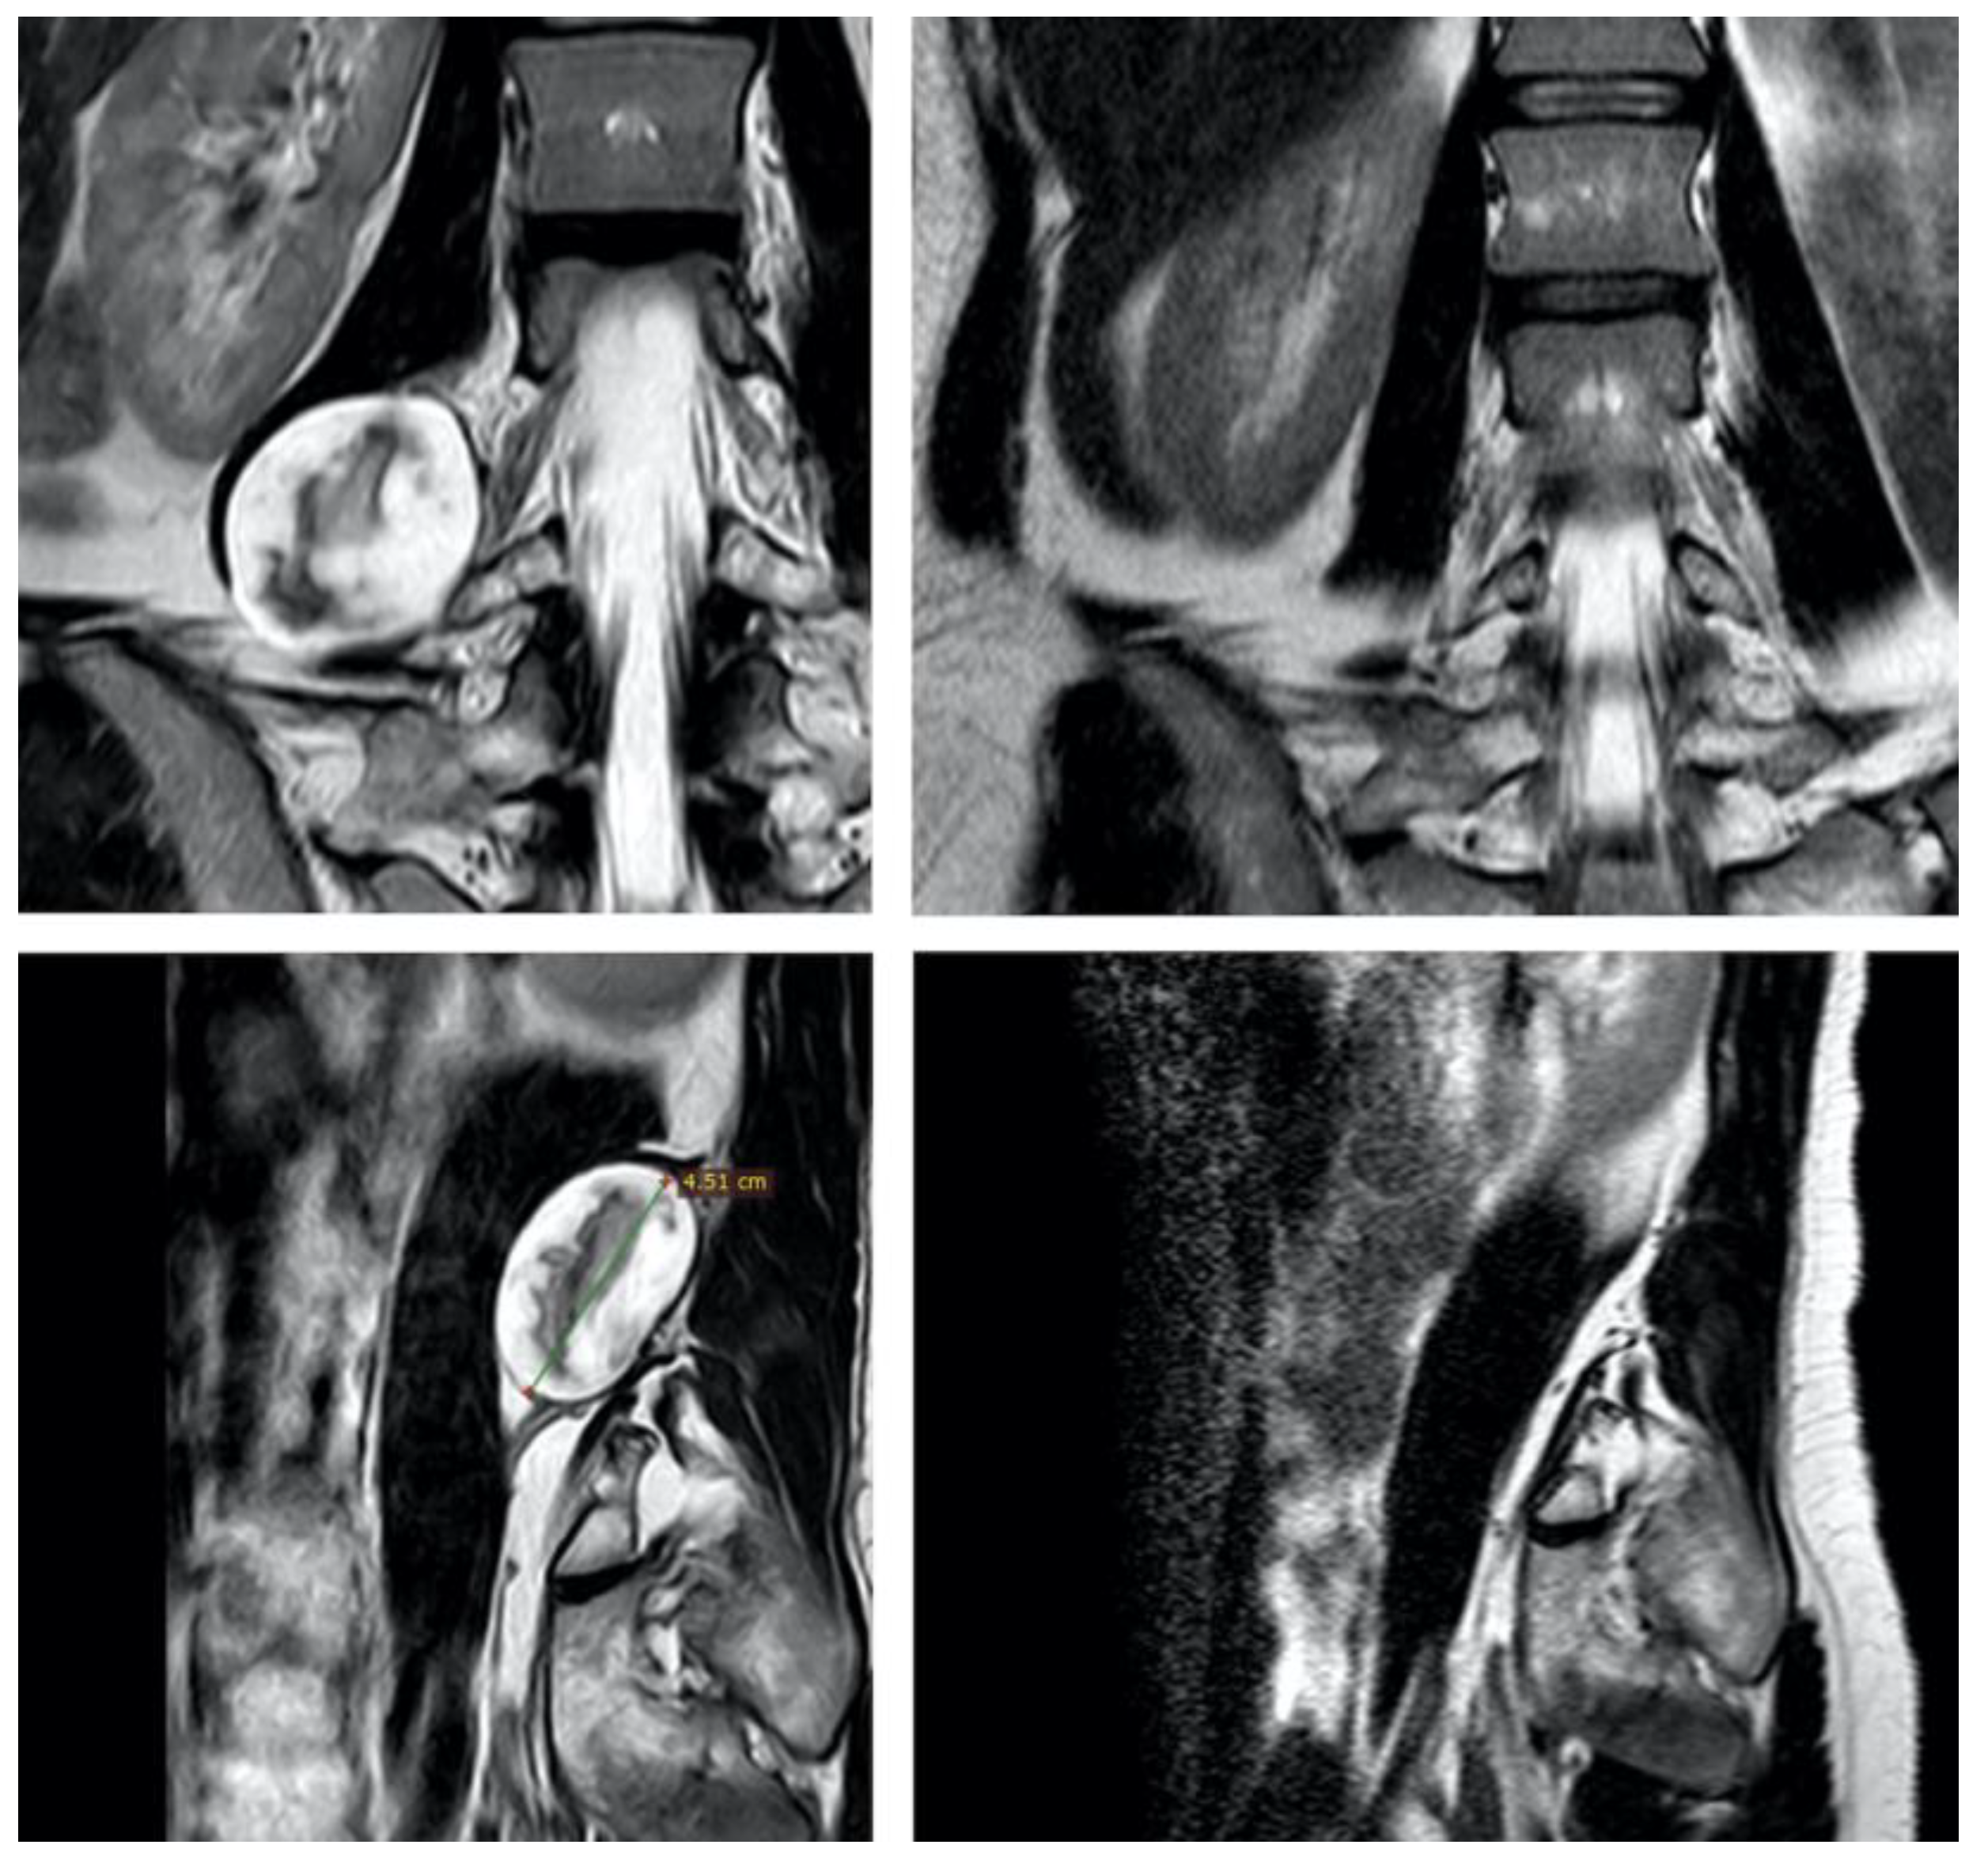

| Patient 5 | 36, F | Sacral plexus (S1-S2), pelvic presacral | S | 130 | Left sciatic hypoestesia | Lower midline laparotomy; retroperitoneal | 480 | 3000 mL; yes | 30 | Ambulating on P.O. day 1; no new deficits; paresthesias on sciatic territory (improving) | Yes; no | Yes (open) |

| Patient 9 | 45, M | Sacral plexus; midline sacral promontory | S | 75 | Lower abdominal pain; abdominal mass | Lower midline laparotomy; transperitoneal | 150 | 200 mL; no | 18 | Ambulating on P.O. day 1; no new deficits | No; no | Yes (percutaneous) |

| Patient 15 | 75, M | Left femoral nerve, lateral to psoas | S | 100 | Left sciatic pain (compression) | Lateral retroperitoneal | 220 | 400 mL; no | 1 | Ambulating on P.O. day 1; no new deficits; pain remission | No, no | Yes (percutaneous) |